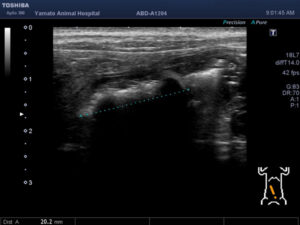

吐き気が続いて、元気・食欲がないワンちゃんが来院されました。超音波検査で異物による小腸閉塞が疑われましたので緊急手術となりました。腸を切開し異物を摘出し、無事手術は終了、元気に退院していきました。よかったね。